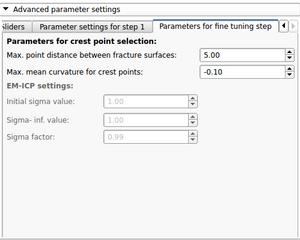

After the first step of the reconstruction is finished and user can inspect the intermediate result. 2D and 3D views will be update according to the calculated transformations. At this point the user, the following scenarios are possible: 1) Good registration - Accept registration without performing further registration (fine tuning part will be skipped). By pressing the "Start fine tuning" button the second part of the reconstruction process in which the fragments will be aligned against each other (without using the reference bone) will be started. The parameters for this step can be changed in the corresponding parameter tab ("Parameters for fine tuning") After the calculations for the fine tuning step are finished, the last tab will be opened ("Result step 2"). Again 2D and 3D views will be updated accordingly and the same 4 scenarios as in the previous step are possible.  Updated 2D and 3D views after final step of reconstruction. Note that the visible gaps are due to missing bone that has been "simulated" in this (toy) example. This view was generated using a wireframe representatioin of the fragments in combination with a volume rendering of CT dataset of the (healthy) reference bone